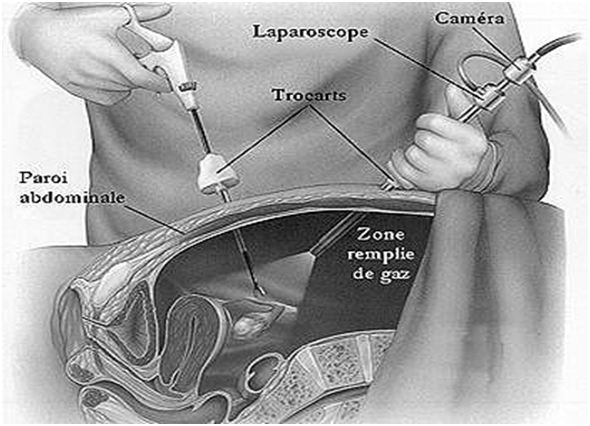

Современные методы лапаротомии и миомэктомии